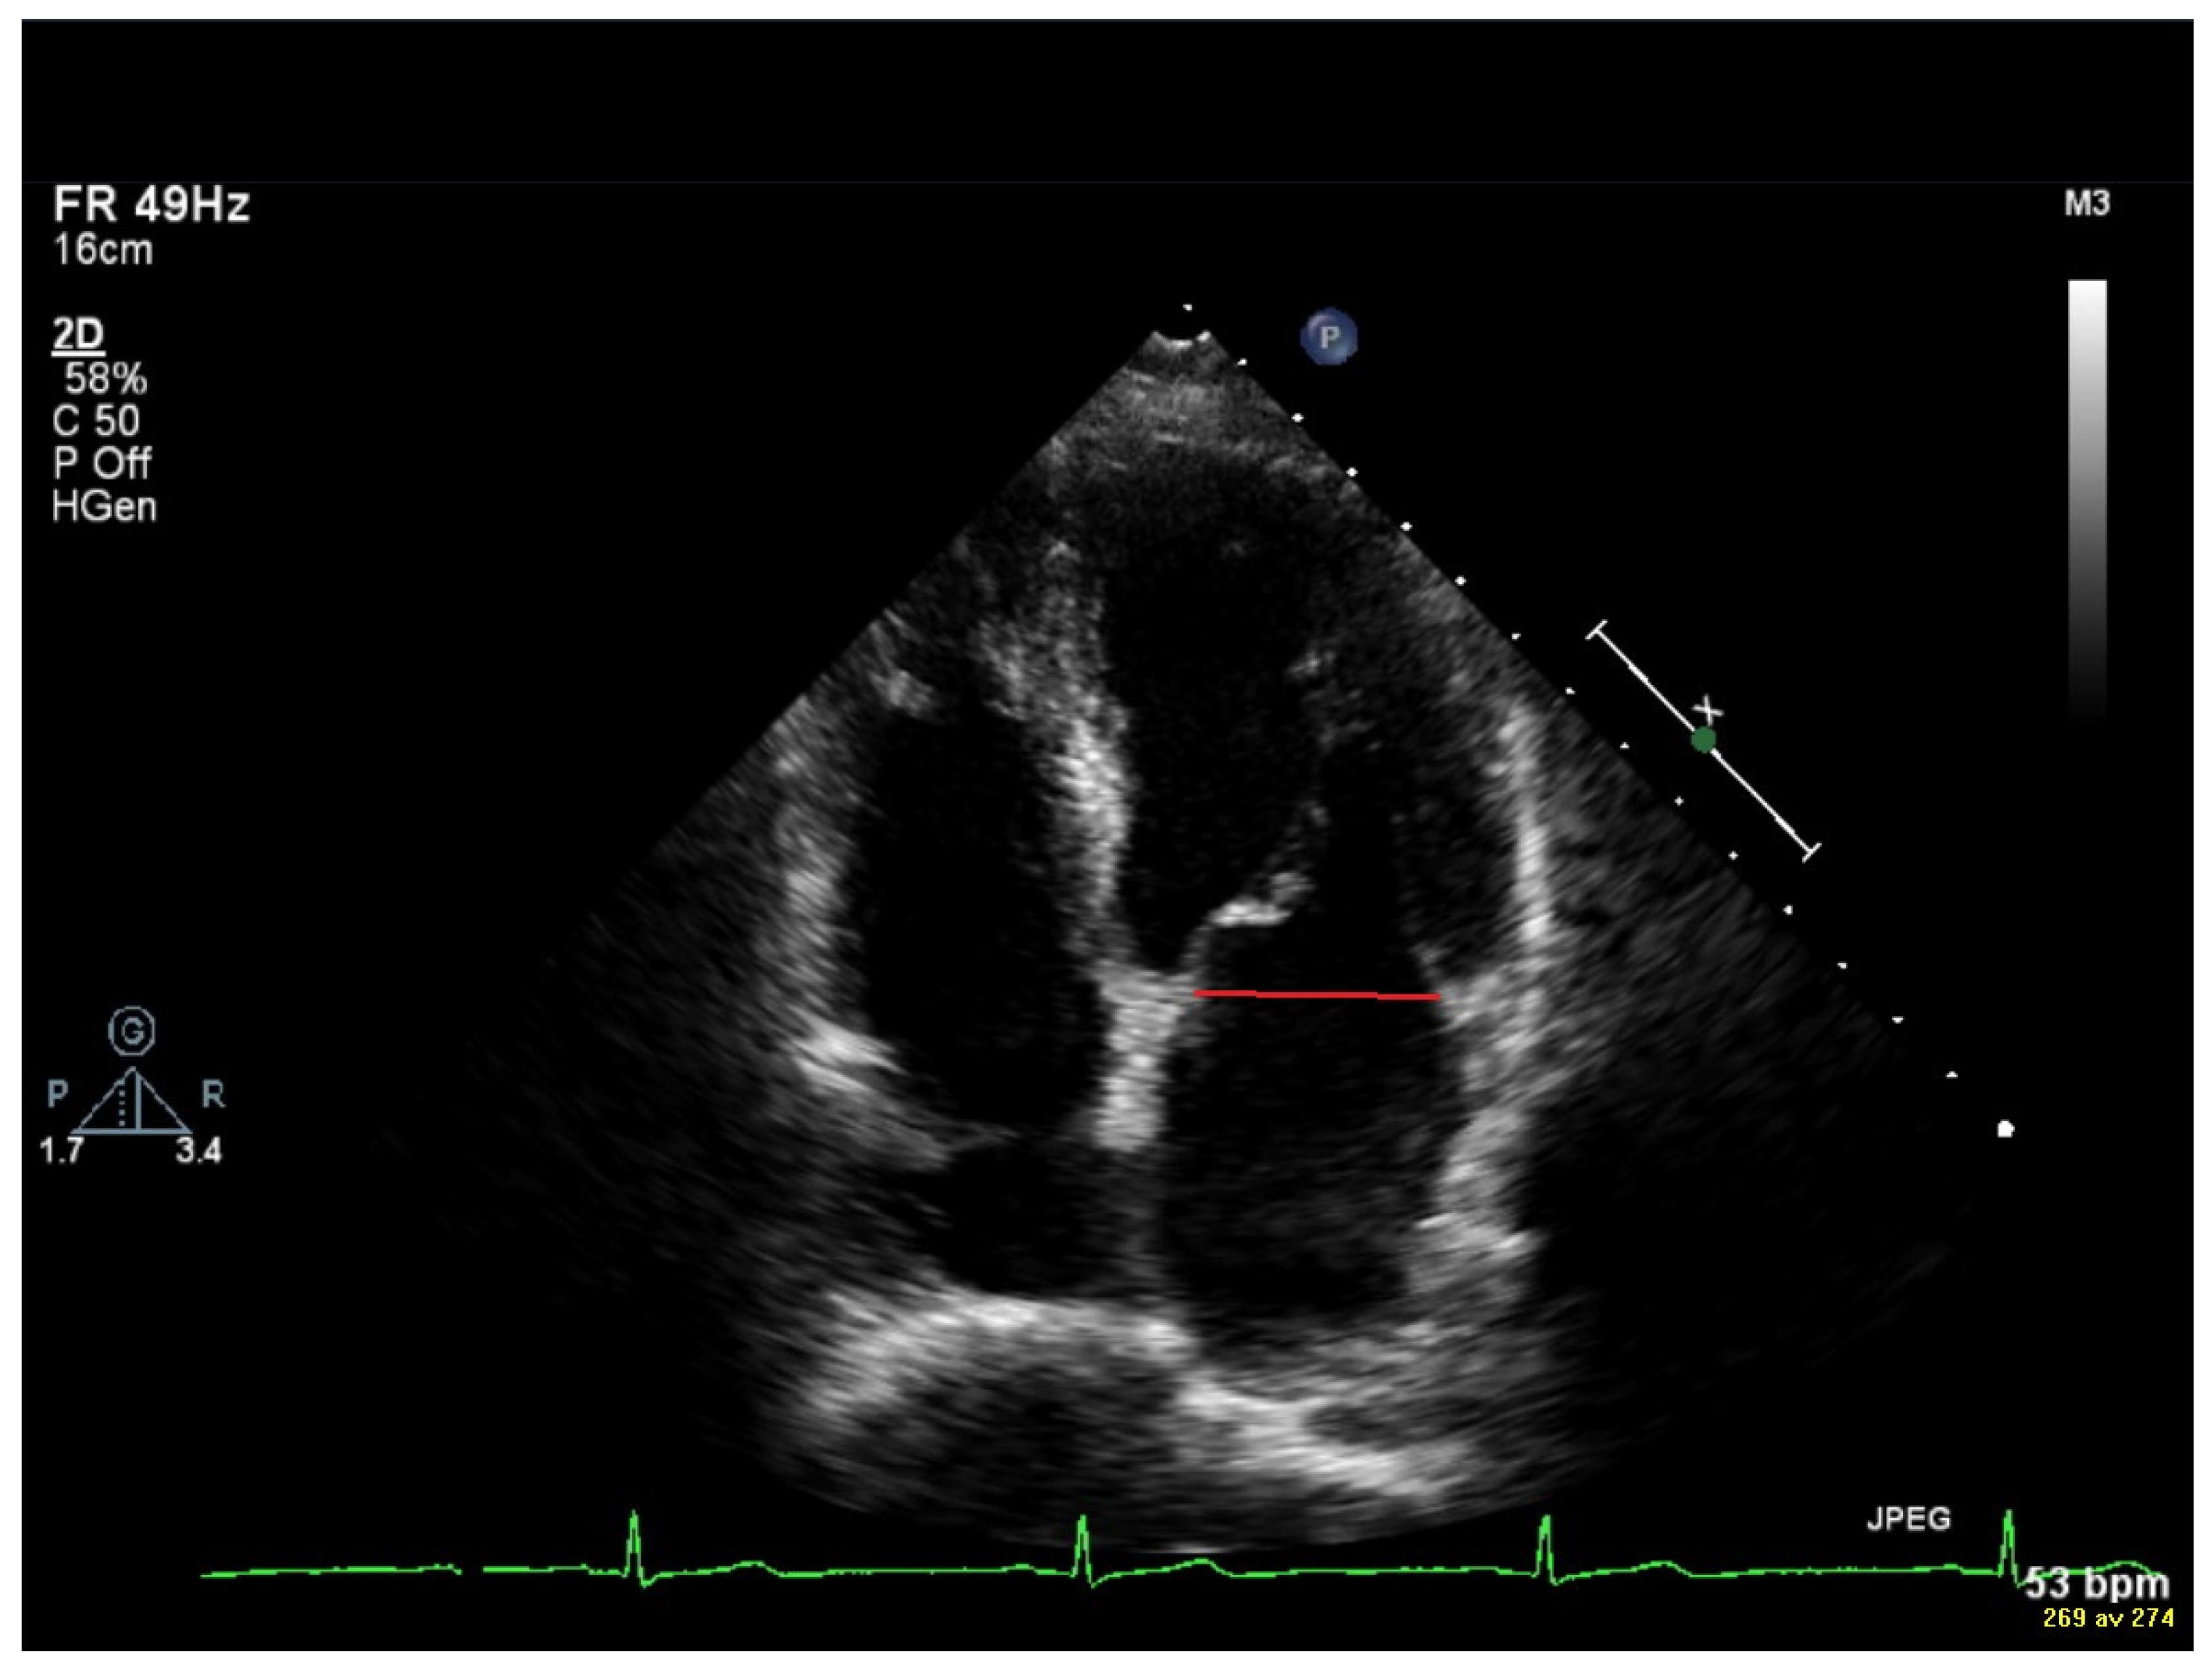

2.3. Vortex Formation and Vortex Formation Time

2.4. Transthoracic Echocardiography (TTE)